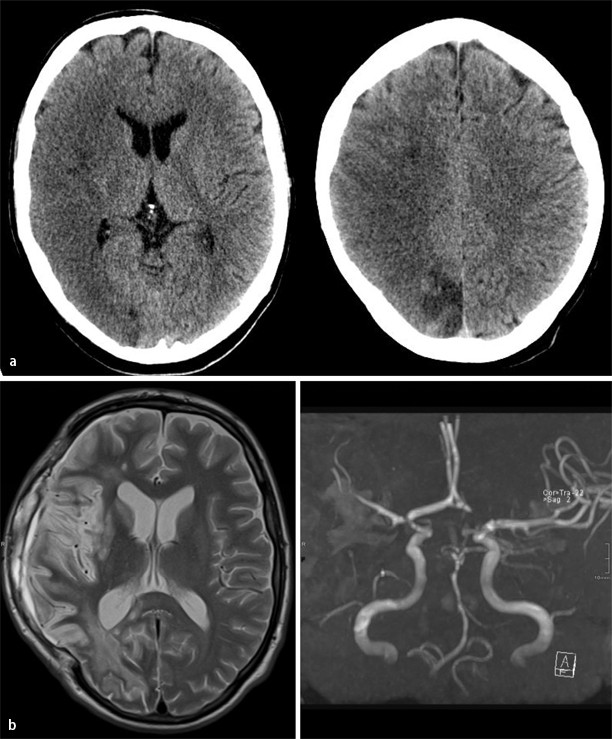

Clinical features of syphilitic myelitis with longitudinally extensive

From www.wjgnet.com

Clinical features of syphilitic myelitis with longitudinally extensive Tabes Dorsalis Syphilis tabes dorsalis, or locomotor ataxia, is a rare neurodegenerative disease caused by an infection with treponema pallidum. tabes dorsalis is a complication of untreated syphilis that involves muscle weakness and abnormal. the term neurosyphilis refers to an infection involving the central nervous system (cns). tabes is characterized by gait ataxia with romberg’s sign (falling or stepping. Tabes Dorsalis Syphilis.

Clinical features of syphilitic myelitis with longitudinally extensive Tabes Dorsalis Syphilis tabes dorsalis is a complication of untreated syphilis that involves muscle weakness and abnormal. tabes is characterized by gait ataxia with romberg’s sign (falling or stepping to one side when standing with feet together and eyes closed) and in most cases by argyll robertson pupils. tabes dorsalis, or locomotor ataxia, is a rare neurodegenerative disease caused by. Tabes Dorsalis Syphilis.